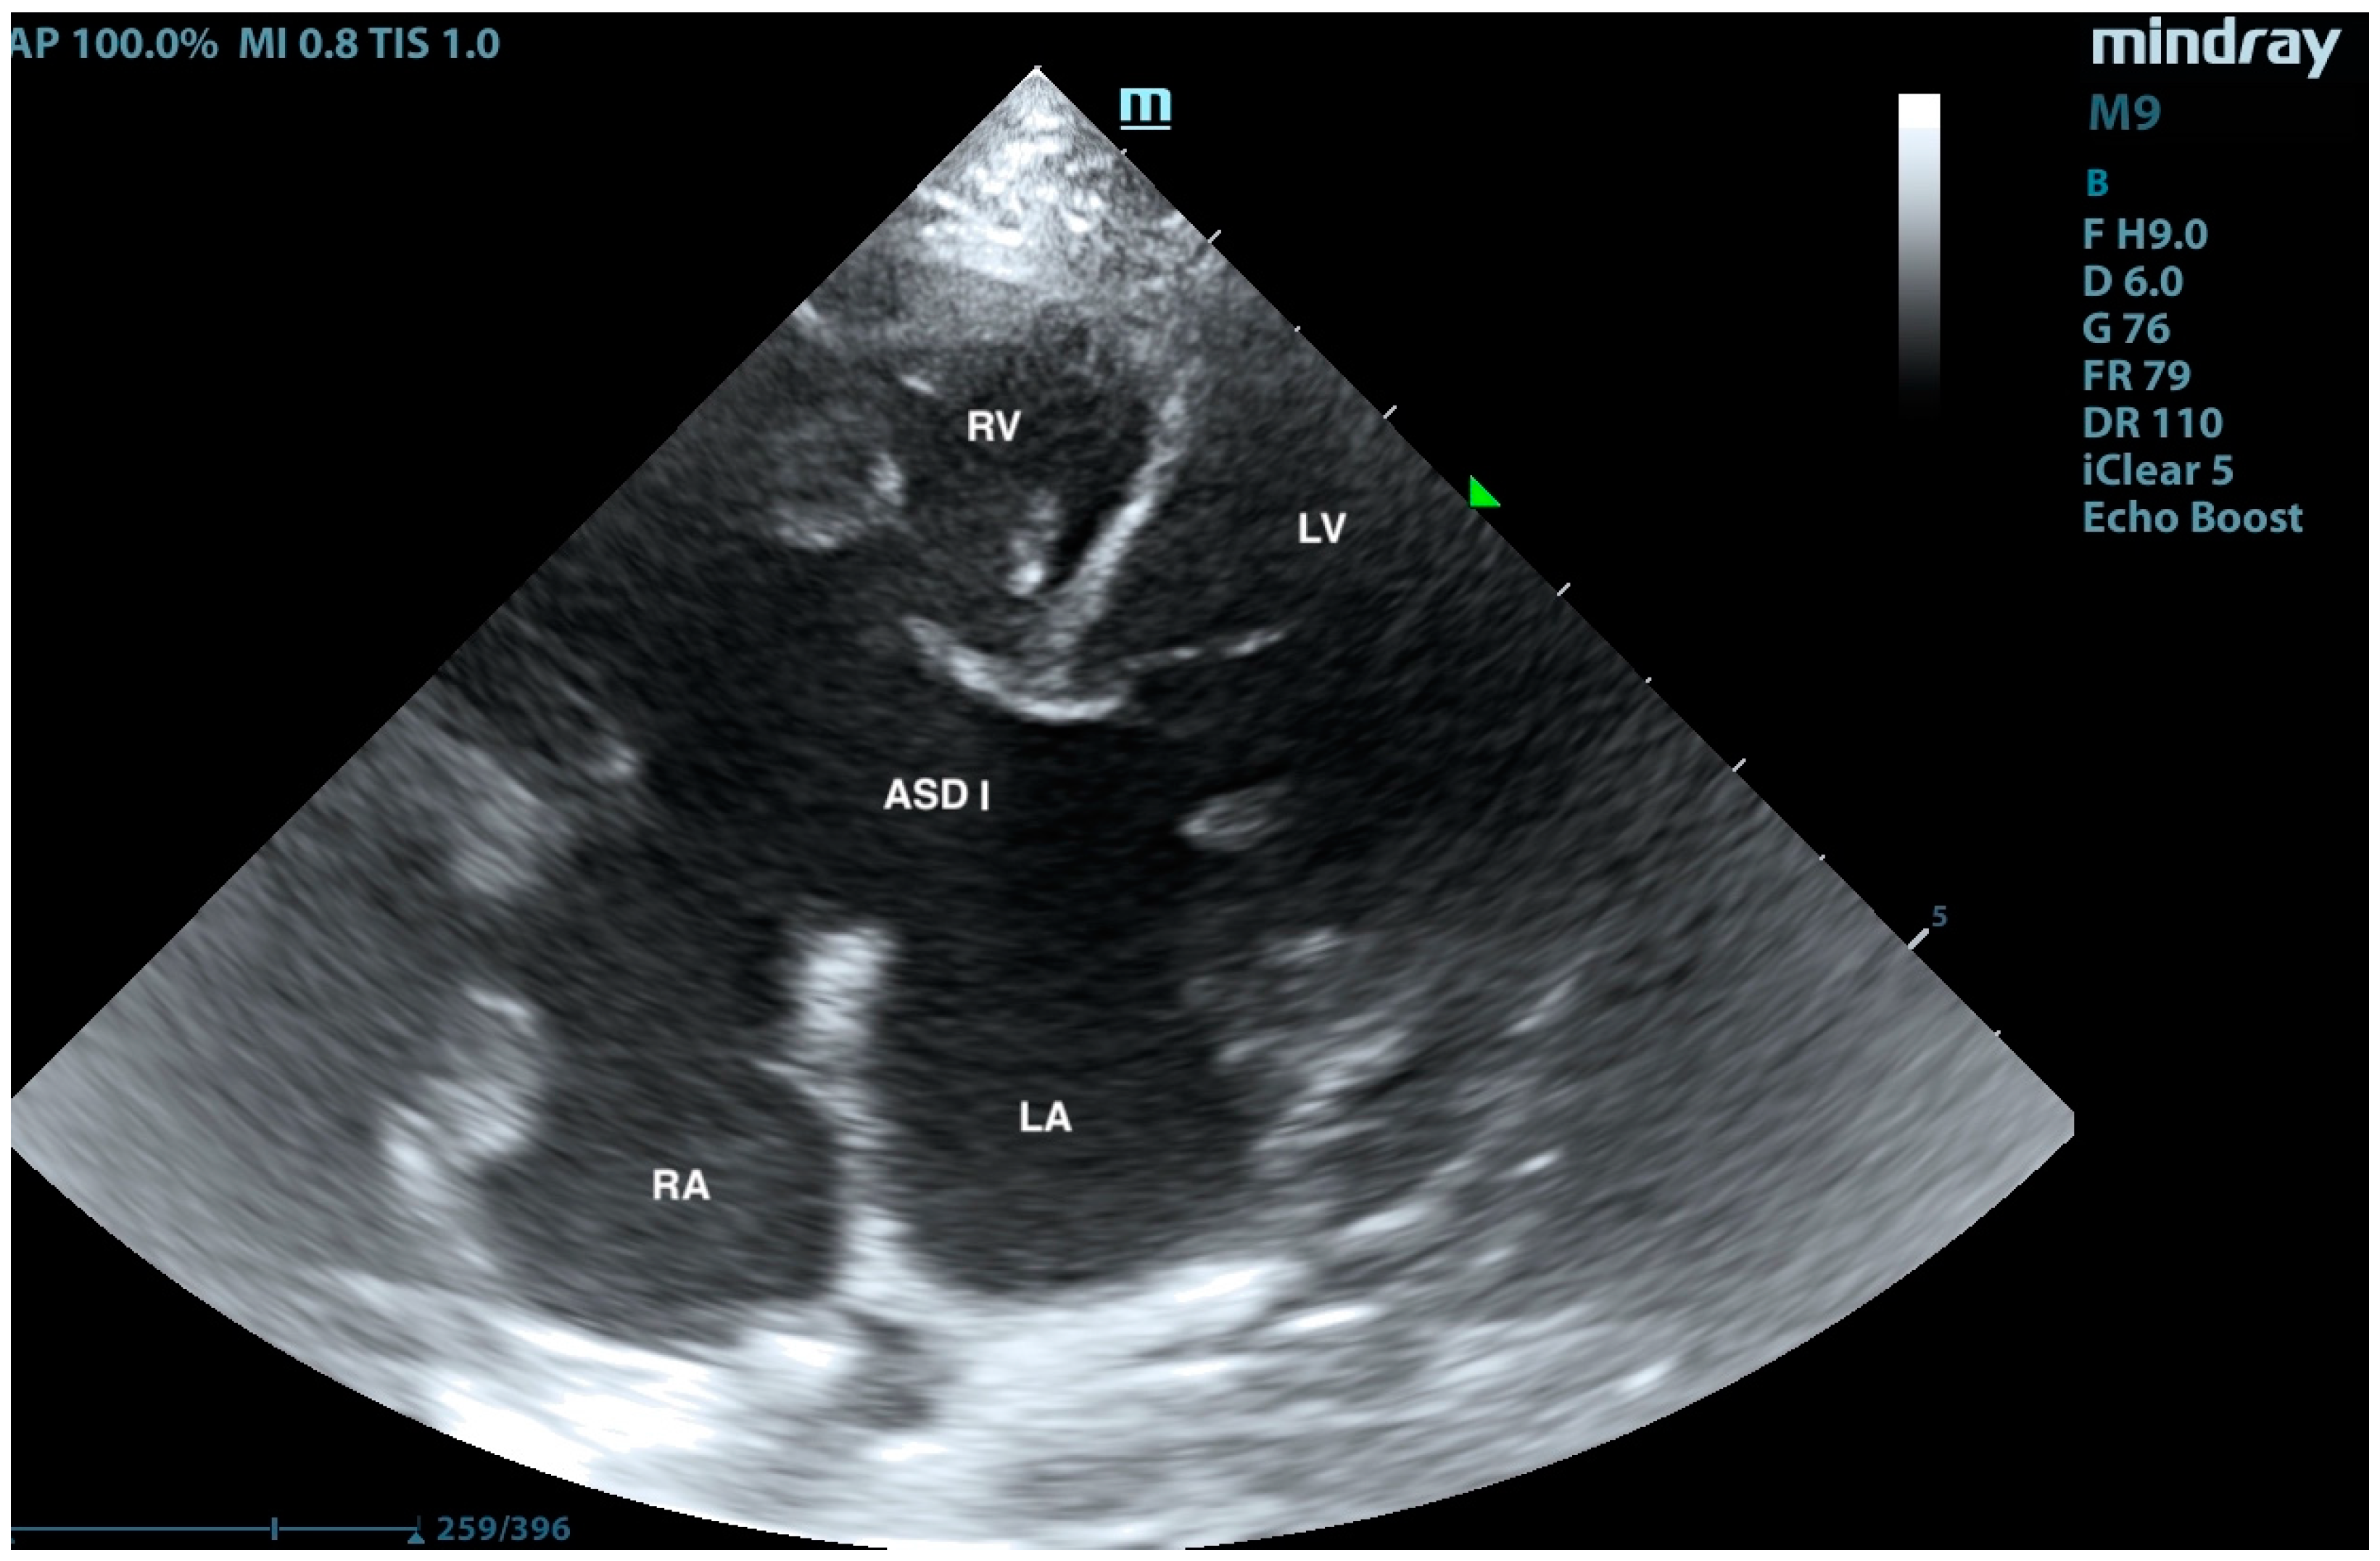

2. Case Presentation